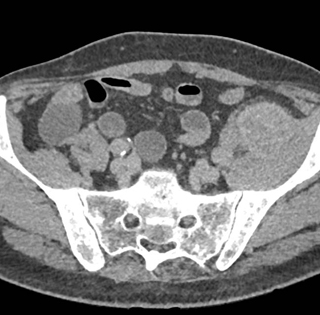

In this patient with left leg pain the best diagnosis is

abscess

hematoma

metastatic lesion to muscle

AV malformation